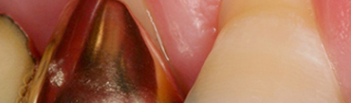

CASE 1 – 치근피개술

치근피개술 치료 전(좌) 치료 후(우)

잘못된 양치질이나 구강관리 또는 이악물기 같은

습관이 반복되면서 위 사진과 같이

잇몸퇴축현상이 일어날 수 있습니다.

대부분 이시림 현상을 겪게 되고,

심미적인 문제로 인해 병원을 찾게 되는데요.

이렇게 잇몸소실로 인해 치아뿌리가 드러난 경우

치근피개술로 개선을 해드리고 있습니다.

이는 입천장 부위의 점막 일부분(구개상피 또는

결합조직)을 채취하여 노출된 치아 뿌리에 덮어

이상적인 잇몸형태로 회복할 수 있답니다.